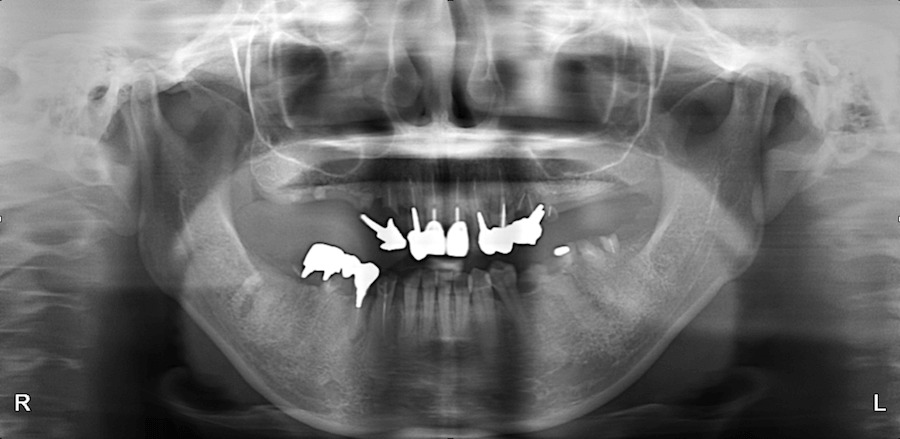

診査診断

治療を進める上で最も重要なステップです。理想的な歯を模型上で Wax-Up します。その後、治療計画を立てていきます。

ラジオグラフィクガイド Radio Graphic Guide

最終的な歯並びを想定したラジオグラフィクガイドという、義歯の様な物を作成し口の中に入れてCTを撮影します。このラジオグラフィクガイドを、いかに正確に作るかが治療の成功の鍵となります。